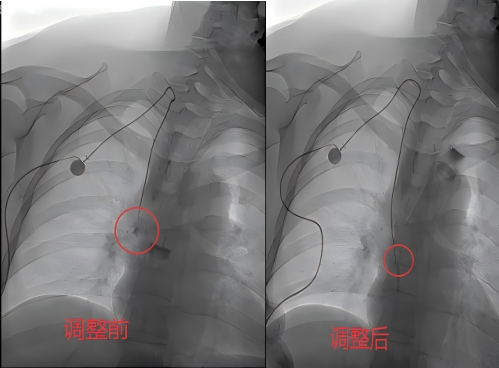

PICC专科护士敖莹进一步完善了通路评估,全面监测患者体征,做好术前心理疏导与用物准备,缓解患者紧张情绪,同步梳理操作配合流程。介入医师张正宇通过DSA血管造影精准锁定问题根源:输液港导管尖端异位进入了奇静脉,导管刺激血管组织,导致患者后背疼痛、输液不畅。

手术中,介入医师张正宇全程把控DSA影像,实时提供高清的血管“导航”;主治医师宋成强在影像引导下,利用生理盐水注射形成的温和水流冲击力,在无导丝介入下调整导管走向;敖莹则全程守护在患者身旁,密切监测生命体征,严格执行无菌操作,精准配合,并实时关注疼痛缓解情况。

协同:多学科协作十分钟打通“生命线” 在三人的默契协作下,仅用数十分钟,原本“跑偏”的导管被精准复位至上腔静脉的理想位置。随着位置修正,张女士后背的疼痛感当即完全消失。术后核查显示,输液港抽回血、输液流速均恢复如常,未出现任何并发症。这条一度“罢工”的生命通路再次恢复通畅,张女士的后续化疗得以顺利重启。

在三人的默契协作下,仅用数十分钟,原本“跑偏”的导管被精准复位至上腔静脉的理想位置。随着位置修正,张女士后背的疼痛感当即完全消失。术后核查显示,输液港抽回血、输液流速均恢复如常,未出现任何并发症。这条一度“罢工”的生命通路再次恢复通畅,张女士的后续化疗得以顺利重启。